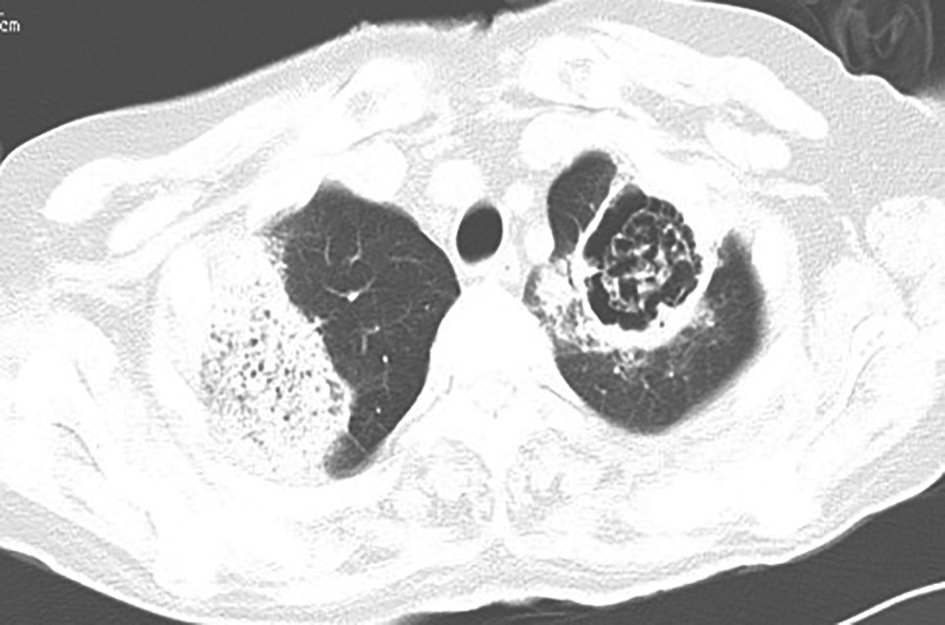

入院前两次胸部CT表现见图1、图2。

图1 发病第20天胸部CT表现

胸部CT可见双肺片状高密度影及多发空洞形成,伴右肺中叶膨胀不全

图2 发病第32天胸部CT表现

胸部CT可见右肺中叶区不张,左肺上叶原空洞部位出现部分实变

4.影像学可见双肺多发片状密度增高影,伴有空洞形成,且短时间内影像学改变明显,由多发斑片影发展为多发空洞,继而出现局部肺不张及实变。

胸部CT见双肺多发片状密度增高影,伴多发空洞形成,并见局限性肺不张及实变。